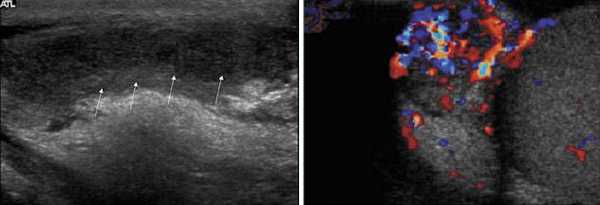

Орхит и эпидидимит - воспаление яичка или его придатка, нередко вызывают формирование реактивного гидроцеле. Кроме увеличения мошонки орхит или эпидидимит может сопровождаться болезненностью мошонки, а также температурой, ознобом дизурией и др. При эпидидимите придаток яичка увеличен в размере и имеет гипоэхогенную структуру. Доплер-УЗИ выявляет усиленный кровоток в области придатка. При орхите яичко на УЗ-изображении имеет гетерогенную структуру.

На рисунках виден увеличенный гипоэхогенный придаток яичка с усиленным кровотоком и небольшого размера реактивное гидроцеле.

Во время ультразвукового исследования с доплером при перекруте яичка определяется нарушенное кровоснабжение яичка, сопровождающееся формированием реактивного гидроцеле, как показано на рисунке.